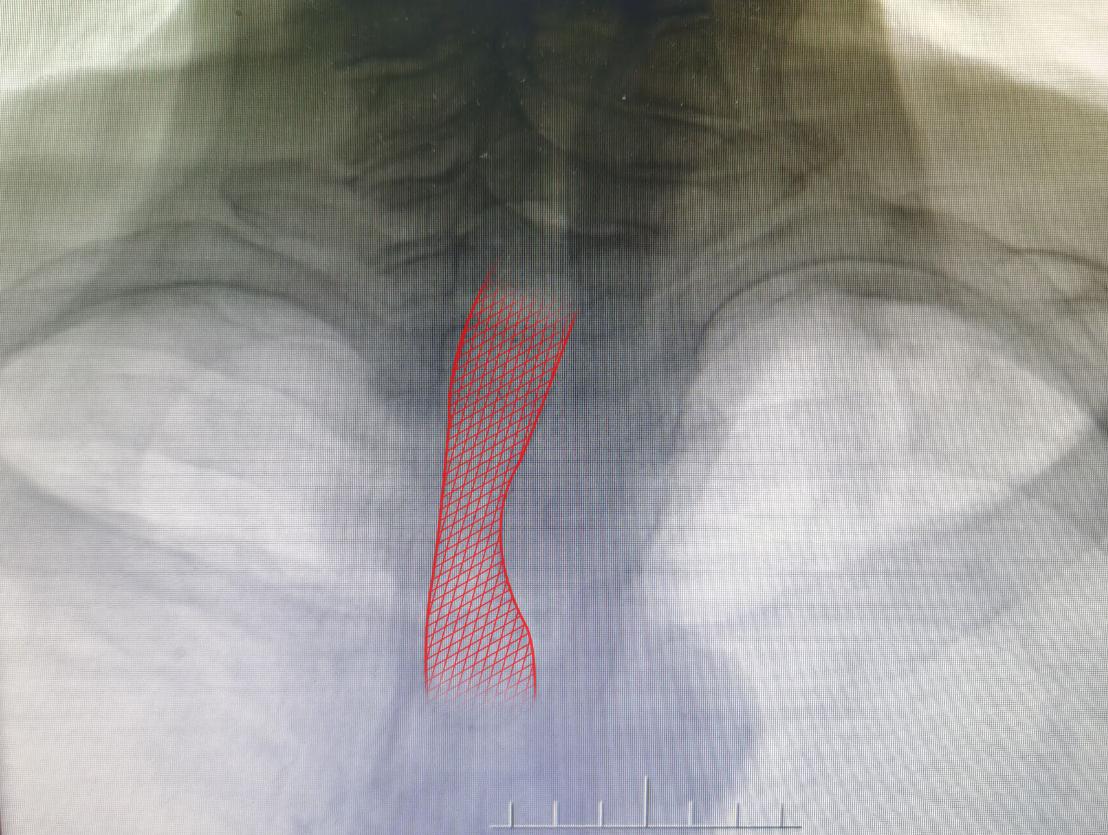

住入肿瘤介入科后,检查发现患者为食管癌致食管气管瘘,患者已无法正常进食,出现气短、咳嗽、咳痰等症状,且因食管气管瘘口的存在,进食食物入肺部导致肺内感染。经肿瘤介入科团队会诊及与患者家属再三沟通后,决定给予患者“食管堵瘘”治疗,在做好充分准备后,介入科团队在DSA引导下行气管支气管支架置入术,术后造影提示瘘口得到有效封堵。患者生命及生活质量明显提高。

植入气管支架

气管支架是一个解决气管腔阻塞或狭窄的假体。气管支架大概从80年代到90年*开代**始在国内应用,发展已经越来越成熟。气管支架置入术是目前较为成熟的一项介入技术,主要运用于急性气道梗阻或严重气道狭窄时,尚可用于治疗食管气管瘘。对于恶性疾病,多无法手术治疗,且药物治疗无法迅速起效,气管支架置入术可作为一项较好的姑息性治疗手段。